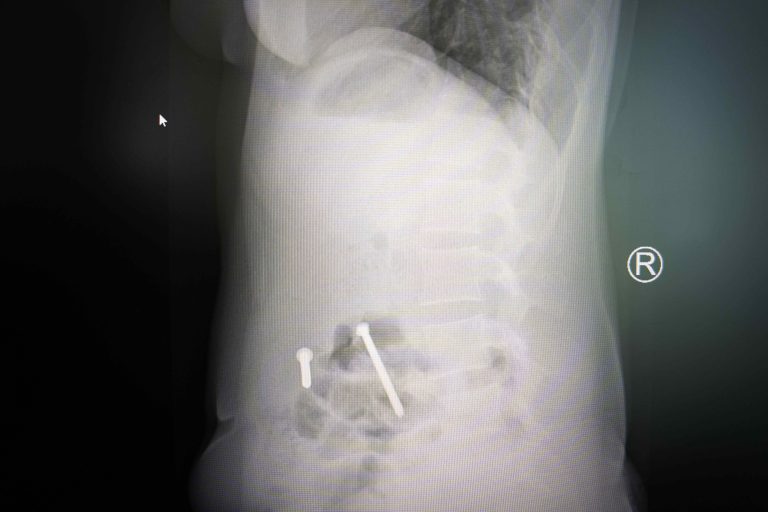

POS MB 708 7X-ray of Eden, a survivor of extreme violence during the war.POS MB 708 7$500

POS MB 708 18X-ray of Eden, war abuse survivor, showing nails inside her body.POS MB 708 18$500